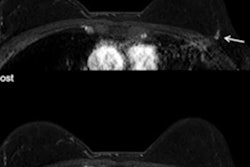

The review included more than a dozen studies evaluating the sensitivity and specificity of an MRI protocol that only used one precontrast image and one postcontrast image, helping to reduce scan time and cost. This shorter, abbreviated-protocol MRI (ABB-MRI) performed the same as a full-protocol MRI (FDP-MRI), suggesting it can be used for diagnostic imaging.

MRI has become increasingly popular as an adjunct imaging method for patients with abnormal mammography or ultrasound findings. While MRI has excellent sensitivity and specificity, a full MRI protocol requires long patient time slots and is more expensive than other imaging methods.

Because abbreviated MRI limits the number of images, it has been proposed as a time-saving and cost-effective alternative to full MRI protocols. Early research has shown that abbreviated protocols perform comparably to full MRI, but no prior systematic meta-analyses had been conducted on the topic, according to the authors.